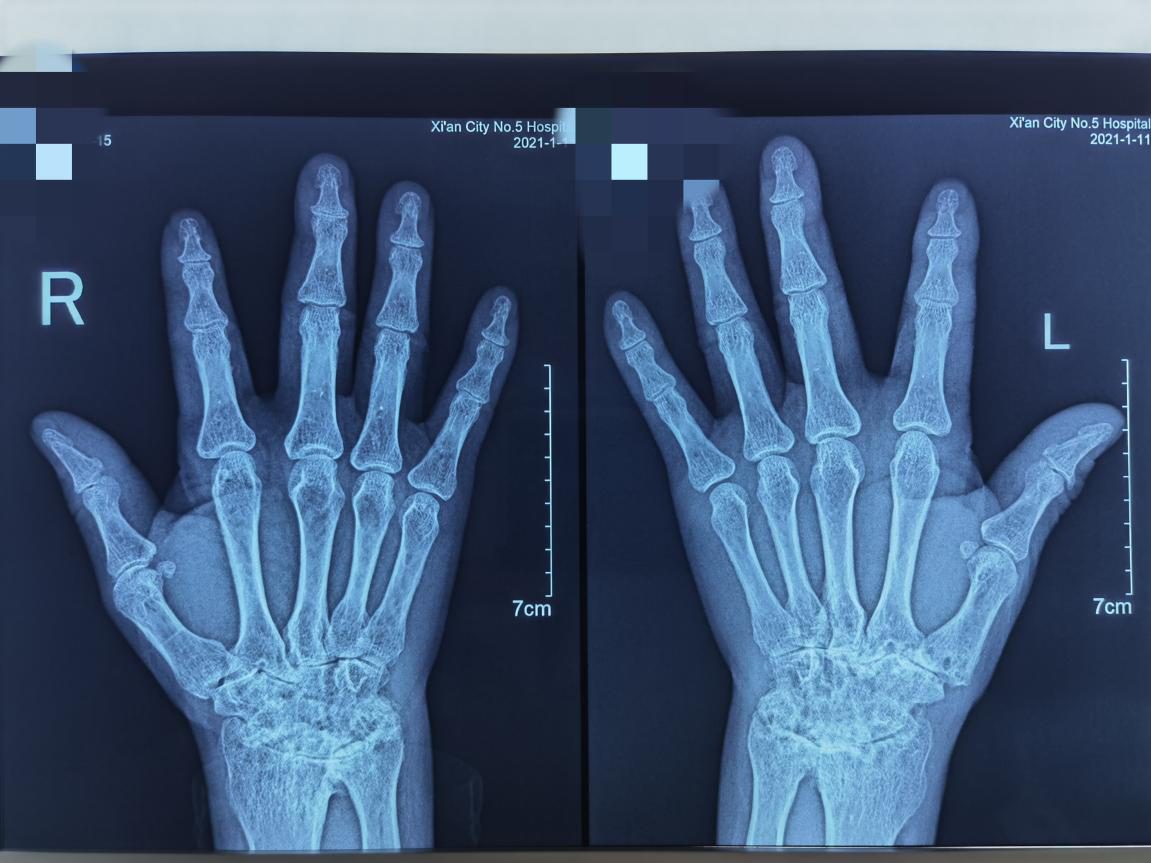

患者代某,20年前无明显诱因出现双腕、双手近端指间指关节、掌指关节、双膝关节游走性疼痛伴肿胀,有晨僵,时间超过半小时。平素患者时有恶风、怕冷。自诉夏天需穿秋衣、秋裤御寒。10余年前曾于我院就诊,化验RF、抗...